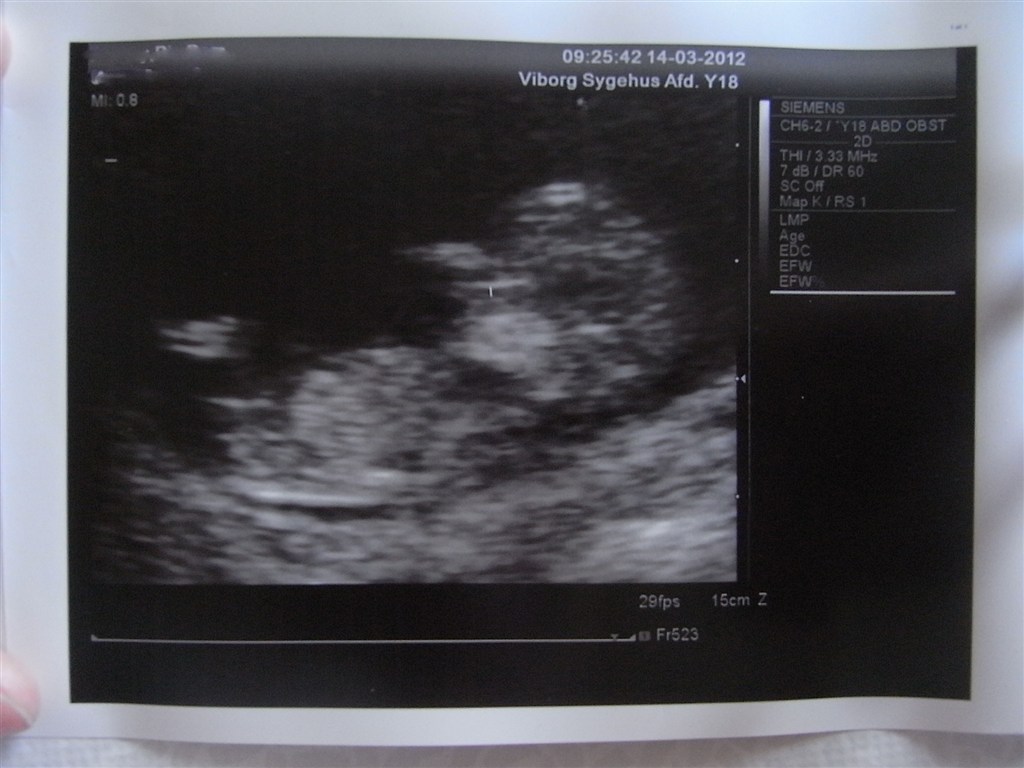

Nå, men bortset fra alle mine regnerier og beregninger omkring termin, var det bare SÅ fedt at se den lille bebs og ikke mindst se det lille hjerte banke.

Til sidst skal I lige se et billede af min lille 4,5 cm. lange guldklump!